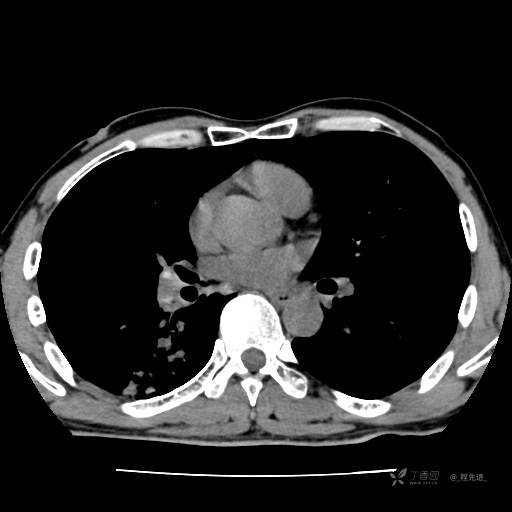

辅助检查:我院门诊胸部CT示:如下。心电图:窦性心律;正常心电图。